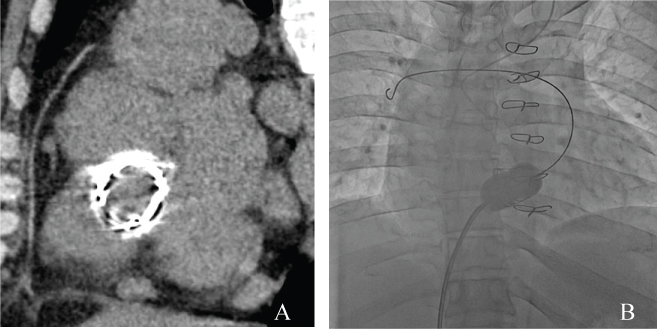

A 38-year-old male presented with right-side heart failure, with symptoms that included dyspnea on exertion, leg edema, and pleural effusion. Soon after birth, he had been diagnosed with incomplete atrioventricular septal defect. At two years of age, a surgical primum atrial septal defect closure, mitral valve plasty, and tricuspid valve plasty were performed. Because he developed severe tricuspid regurgitation at the age of five, a tricuspid valve replacement with a mechanical prosthetic valve (SJM27 mm) was performed. At the age of 20, stuck-valve and severe tricuspid stenosis occurred, and he underwent a second tricuspid valve replacement with a bioprosthetic valve (CEP27 mm). During surgery, an expansive pannus was observed. At the age of 29, the patient ceased medical follow-up. On admission, his physical examination revealed moderate edema in both legs. A Levine Grade III/VI, diastolic rumble also was auscultated at the lower left sternal border. A transthoracic echocardiogram revealed severely calcified, thickened, and immobile leaflets of the bioprosthetic tricuspid valve (Figure 1A, Movie 1). The peak velocity was 2.5 m/sec with a mean diastolic gradient across the tricuspid valve of 14 mmHg (Figure 1B). Tricuspid regurgitation was mild. An invasive hemodynamic study by cardiac catheterization revealed 9.8 mmHg of mean transvalvular pressure gradient and mean right atrial pressure that had elevated to 17 mmHg. The tricuspid valve area was measured as 1.0 cm2 by Gorlin's equation (Figure 2A). He also had two major comorbidities. The first was hepatic cirrhosis due to the hepatitis B virus and a congestive liver; the second was a progressive post-mediastinum tumor, the size of which was 50 × 55 mm. His fourth sternotomy was considered a high-risk procedure. His hepatic function also was thought to be insufficient for highly-invasive surgery. Therefore, the patient was offered a percutaneous transcatheter tricuspid balloon valvuloplasty, a less-invasive procedure.

A 14-Fr long sheath was inserted via the right femoral vein and the guide wire passed through the bioprosthesis to the right pulmonary artery. A 26 mm Inoue balloon (Toray Medical Ltd., Japan) was inflated to a maximum of 26 mm, equivalent to 96% of the bioprosthetic valve (Figure 3A and Figure 3B). After the procedure, mean transvalvular pressure gradient decreased to 5.3 mmHg, mean right atrial pressure was then reduced to 15 mmHg and the tricuspid valve area increased to 1.3 cm2 (Figure 2B). The echocardiogram revealed that peak velocity had decreased to 1.7 m/sec, with a mean diastolic gradient of 7.5 mmHg (Figures 1C and Figure 1D, Movie 2). Deterioration of tricuspid regurgitation did not occur.

Figure 3: A) CT image before the valvuloplasty shows a highly calcified bioprosthetic valve in the tricuspid position; B) Fluoroscopic image in the anterior-posterior view shows the stiff guide wire passing through the center of the deteriorated bioprosthetic tricuspid valve, with the wire tip in the right pulmonary artery. A balloon valvuloplasty was performed using an Inoue balloon (maximum diameter 26 mm). View Figure 3